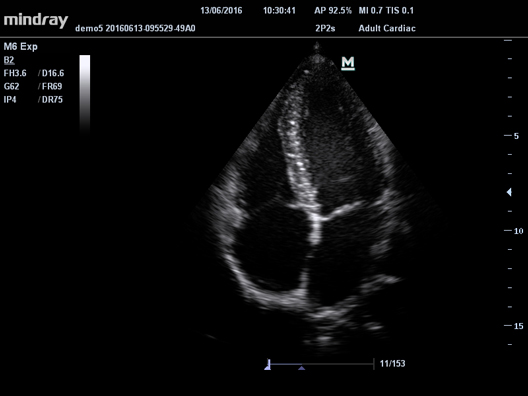

УЗ-сканер Mindray М6 exp представляет собой полнофункциональную портативную, размером с ноутбук, систему цветной допплерографии. Аппарат обеспечивает безупречную визуализацию в формате 2D. Оснащенная специализированными технологиями система М6 exp является оптимальным вариантом для применения.

Характеристики

Тип

- Портативный

Класс

Средний

Области применения

- Общая визуализация